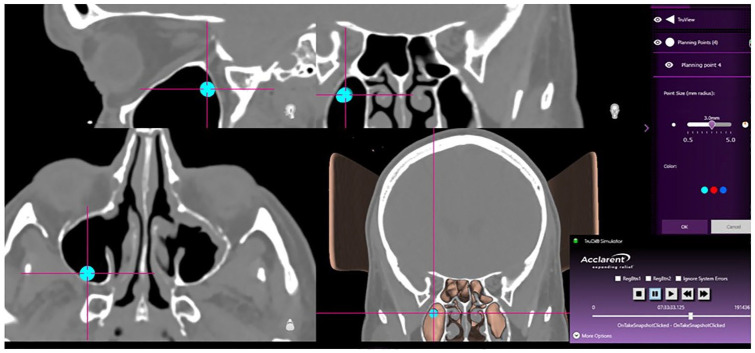

Methods: The TruDi navigation system (Acclarent, Irving, CA) was registered using a contour-based protocol. The surgeon estimated target registration error (e-TRE) at up to 8 points (anatomic regions of interest [ROI]) during endoscopic sinus surgery (ESS). System logs were used to simulate the localization for quantitative assessment of TRE (q-TRE).

Abstract Image